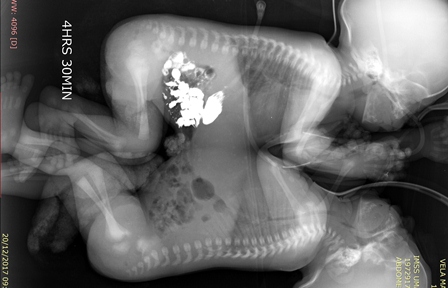

Tras diversos exámenes de tomografía, ecocardiograma y resonancia magnética, cuando los niños cumplieron 41 días de vida, fueron programados para la cirugía que los separaría.